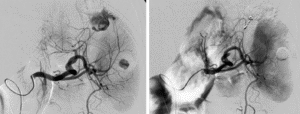

Les radiologues interventionnels utilisent des techniques d’imagerie (échographie, scanner, angiographie) pour réaliser des procédures mini-invasives à visée thérapeutique qui viennent en complément ou en alternative à la chirurgie.

Ces techniques permettent de traiter diverses pathologies sans nécessiter de grandes incisions, les patients n’ont donc pas de cicatrice au décours de l’intervention. Les procédures de radiologie interventionnelle sont souvent moins risquées et plus rapide que la chirurgie traditionnelle.